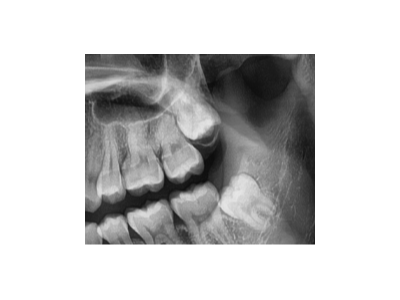

智齒又被稱為第三磨牙,一般有1~4顆不等。由于生長空間有限,很多智齒無法正常萌出,它會歪著長、橫著長,甚至野蠻生長……